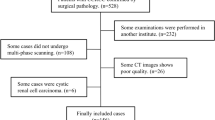

All retrieved CT images were stored in anonymized DICOM format. ITK-SNAP software (http://www.itksnap.org) was used to delineate target 3D VOI on the CT slice of the tumor in phases 1–4 for tumor segmentation. First, a contour-focused lesion VOI was manually delineated on the NP and then applied to the other 3 phases with slight adjustments tailoring VOIs to each phase. Next, a larger VOI containing perirenal fat and peritumoral renal parenchyma was generated by dilating the contour-focused original VOI by ~ 1 cm. This process was not entirely isotropic as the dilation would stop when encountering the bowel, liver, spleen, adrenal gland, vasculature, lymph nodes, adjacent visceral, or muscular tissue. Subtraction of the 2 VOIs yielded a loop VOI (VOI_loop), which was automatically divided into 2 parts of perirenal fat (VOI_loop_fat) and peritumoral renal parenchyma (VOI_loop_margin) using a predefined Hounsfield unit (HU) threshold of − 20. The VOI_loop_fat (< − 20 HU) or the VOI_loop_margin (> − 20 HU) was post-processed by removing isolated parts and filling small cavities. Manual segmentation was done by 2 investigators without prior knowledge of the lesions’ pathology (S.W. Luo and R.L. Wei, with 4 and 5 years of experience in radiological diagnosis, respectively). Conformity of the delineated VOIs was measured using Dice similarity coefficient. For those CT slices with Dice indexes > 0.9, the unanimous segmentation was the intersection of the two individual segmentations, while for those slices with Dice < 0.9, discrepancies on lesion boundary were resolved by further discussions to reach consensus.